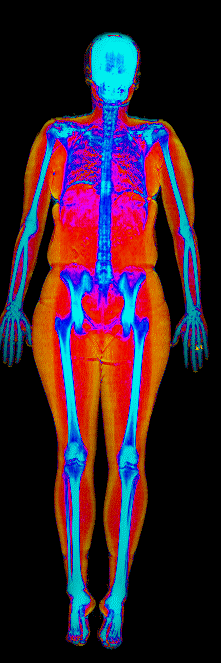

What Fat Loss Looks Like on a DEXA Scan

Red = muscle, gold = fat, blue = bone.

Lost 26.0 lb of fat · 187 → 150 lb · Age 44

Lost 25.4 lb of fat, gained 3.7 lb lean · 201 → 180 lb · Age 33

Lost 24.9 lb of fat, gained 12.0 lb lean · 183 → 170 lb · Age 37